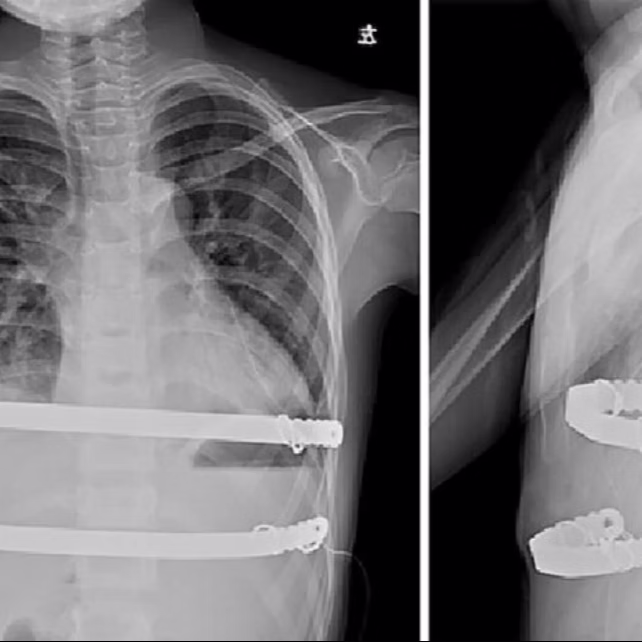

Bars implanted inside the body during the Nuss procedure. Extensive clinical practice shows that the bars inside the body usually do not...

Different Technique for bar placement: The Nuss procedure involves placing steel bars with thoracoscopic assistance. However, when the...